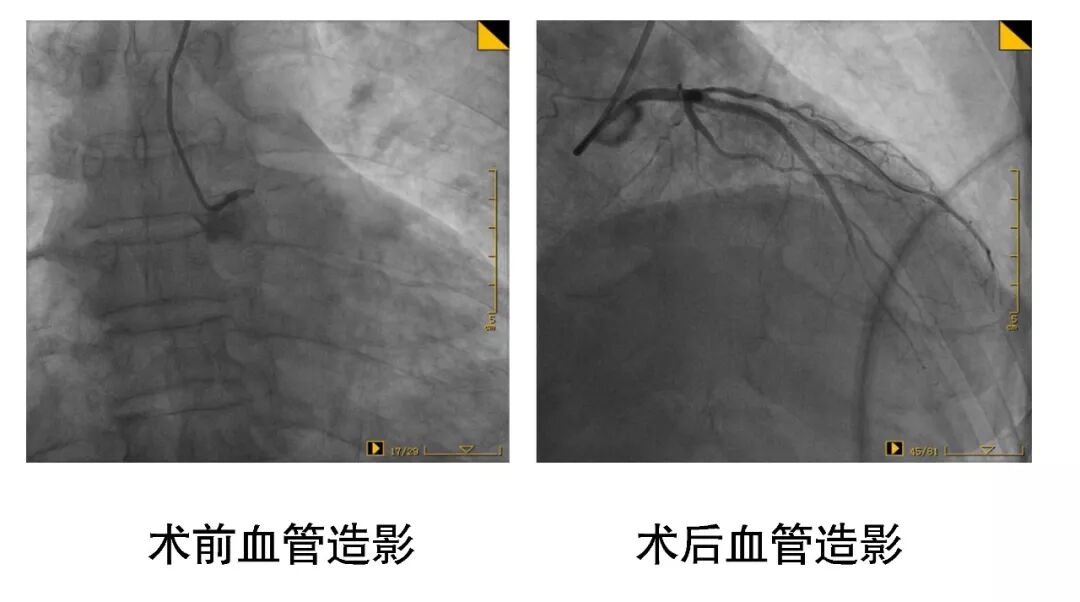

近日,桓台县人民医院心内科一病区介入团队成功为两例心脏冠脉左主干严重狭窄患者实施介入支架置入手术。

两例患者因胸闷胸痛在外院治疗效果不佳,转入我院就诊。造影结果显示两例患者均为左主干严重病变。其中一例患者,因先天性右冠脉、回旋支发育短小,所以左主干供血范围巨大,一旦左主干发生病变,将危急生命。另一例患者左主干完全闭塞!患者能自主来院已经是个奇迹了。两例患者随时有生命危险,必须立刻进行手术治疗! 在和患者及家属充分沟通后,王磊主任带领心内科一病区介入团队分别为两例患者实施介入支架置入手术,开通了闭塞血管,患者胸痛症状当即缓解,转危为安。 病例一 病例二 据王磊主任介绍,心脏冠脉左主干是心脏供血的“总闸门”,一旦发病,多数表现为猝死,死亡率高达80%以上。一旦出现胸痛症状,切勿大意,应及时就医以便早发现早治疗。